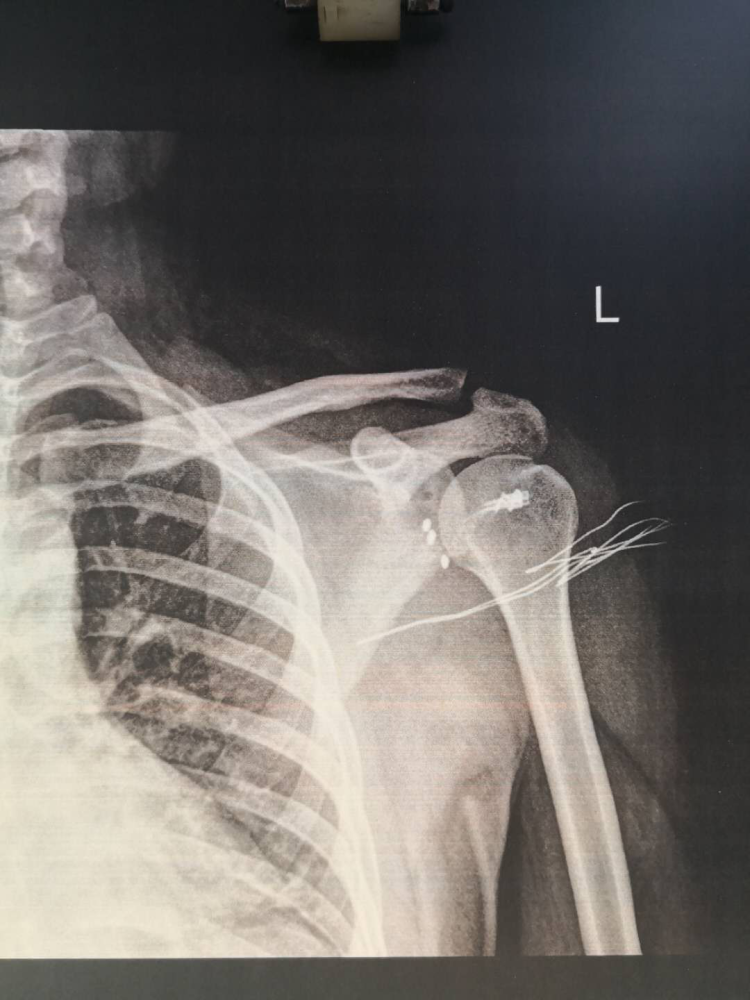

男子骑摩托不慎摔伤左肩肩关节畸形疼痛难忍专家提醒这个症状没那么

3,肩三角肌塌陷,呈方肩畸形,在腋窝,喙突下或锁骨下可触及移位的肱骨

方肩畸形(图 2),肩胛盂处有空

两边比较着看会更清楚,右边"方肩畸形",脱位明征, 左边肩部明显的圆顿